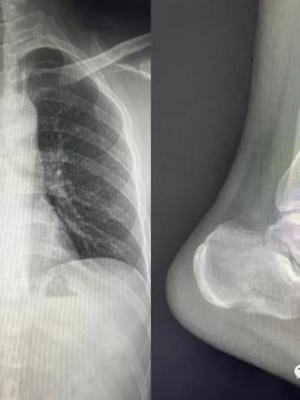

X线腹部检查临床应用及图像表现少钱

临床应用

胃肠道检查费、骨骼系统和胸部多疾病优先选用危害。

图像表现